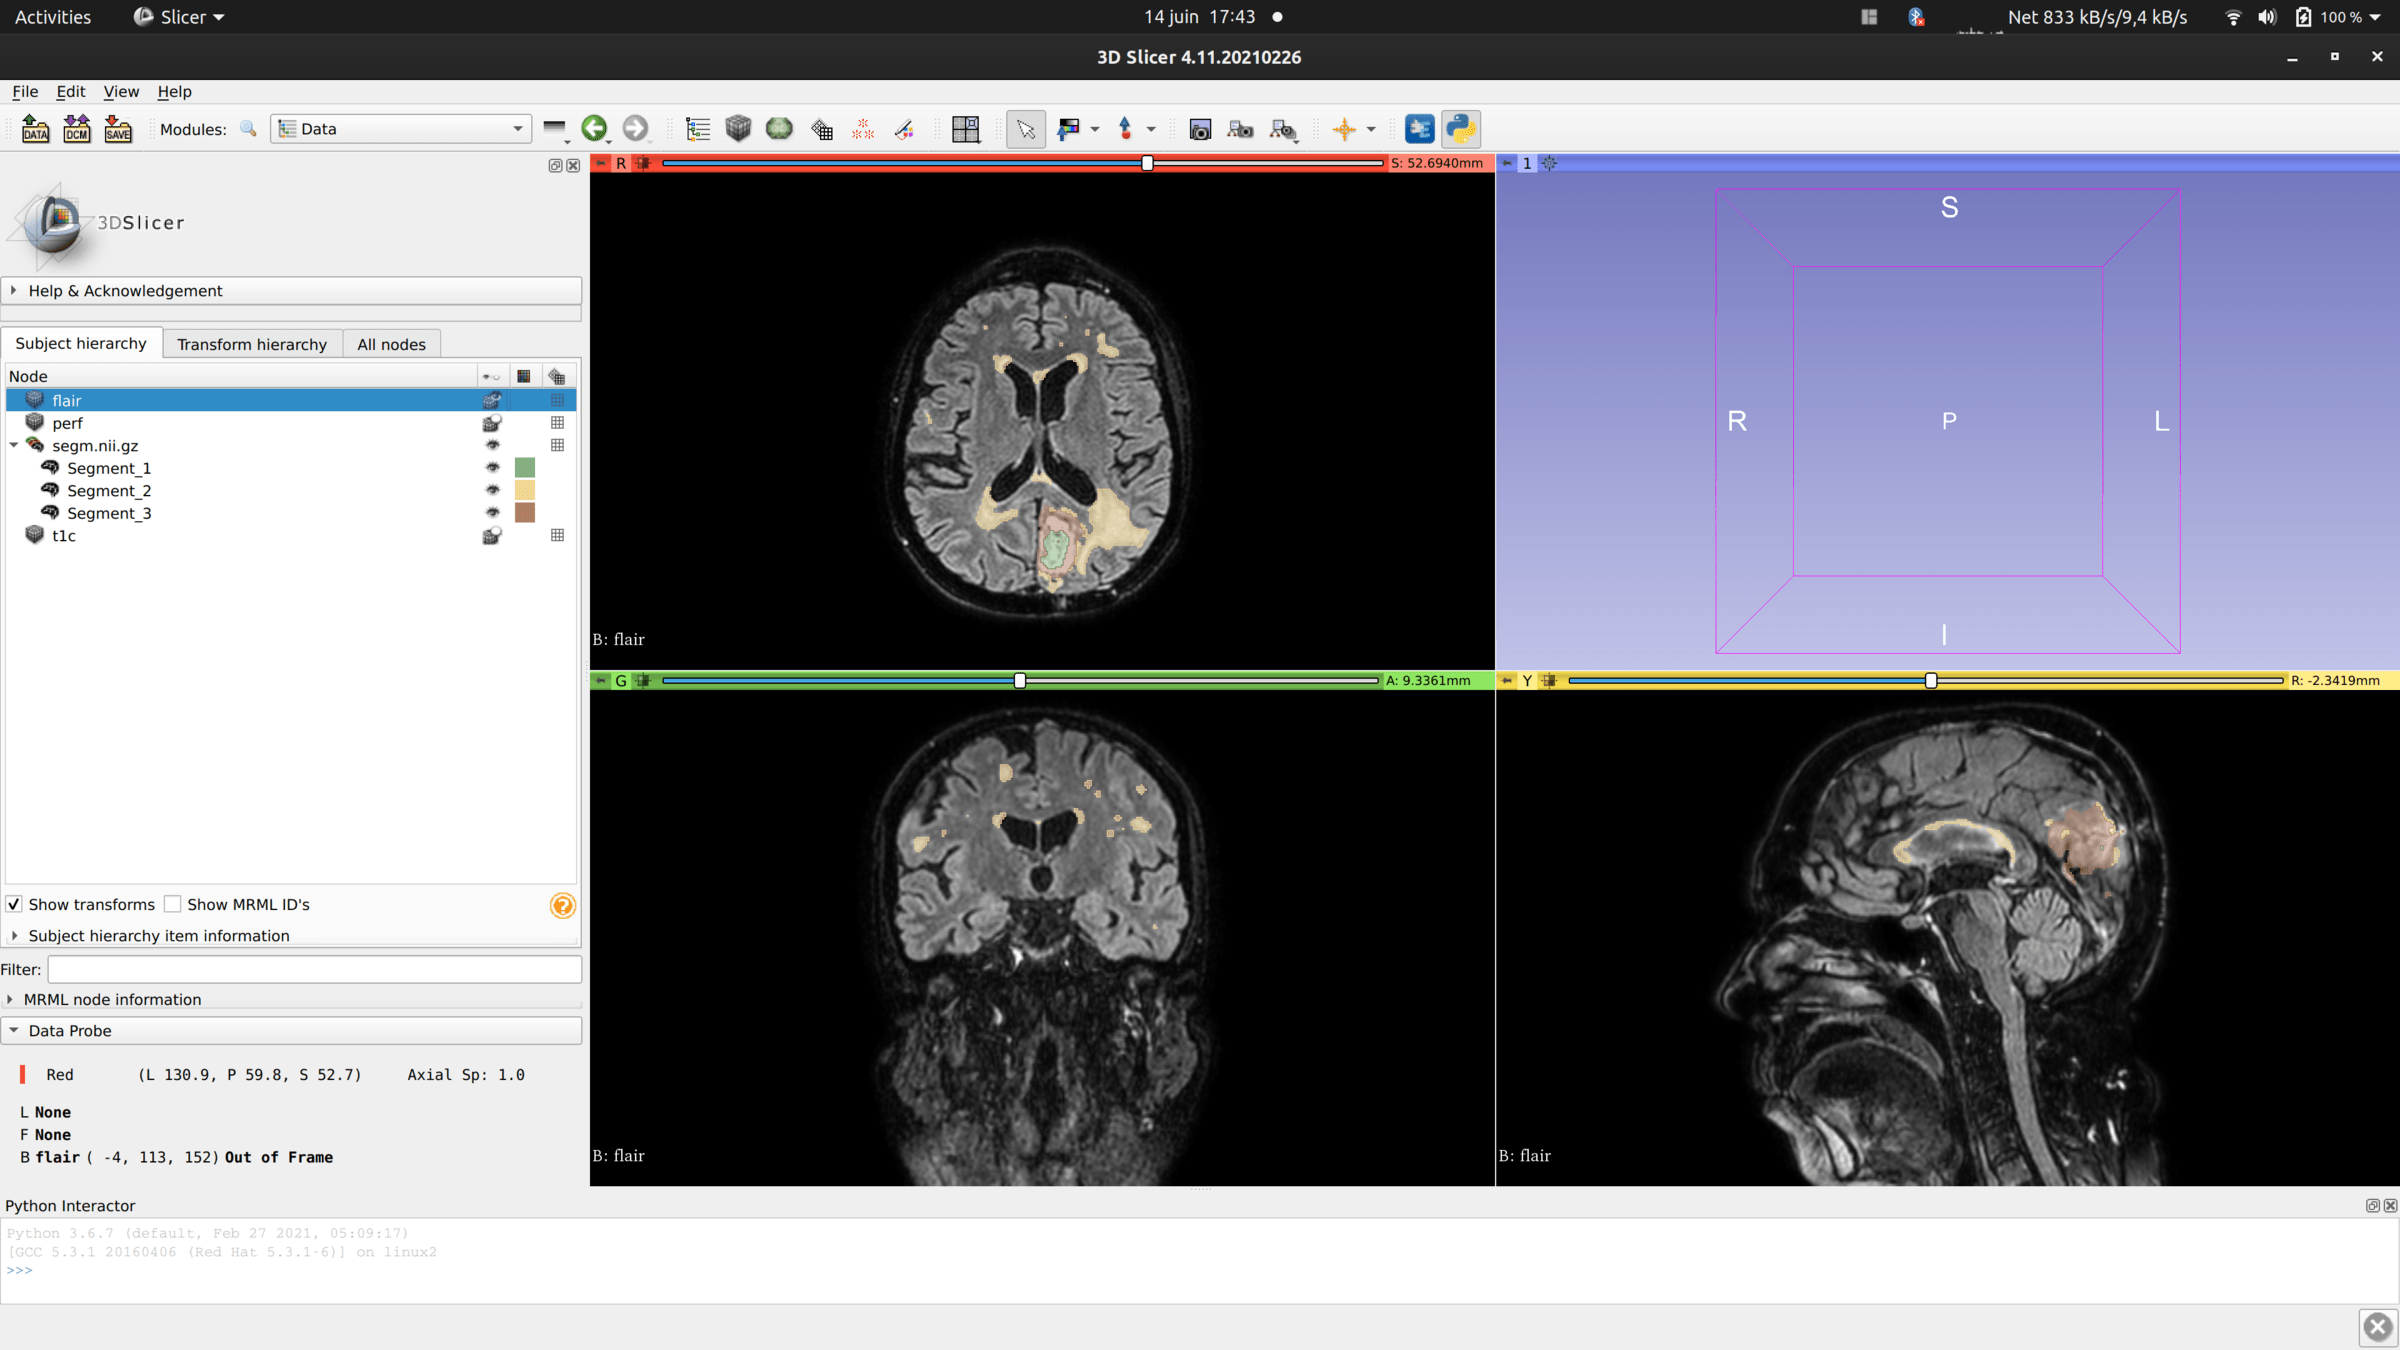

Données RadioAide

Shanoir

Données Pixyl: Itération 01

•  7 patients

• Longitudinal - Entre 5 et 23 images à des temps différents par patients (1tps = 1 dossier)

• Entre deux pas de temps, cerveau non recalés rigidement

• Chaque dossier comprends:

• Image FLAIR - Avec le crane

• prev_flair - ressemble à un préprocessing de l'image FLAIR (Crâne moins intense; hyperintensité moins fortes aussi)

• prev_segm - segmentation

• prob - probabilité / carte (presque) entre 0 et 1 à l'emplacement des WMH

• segm - segmentation